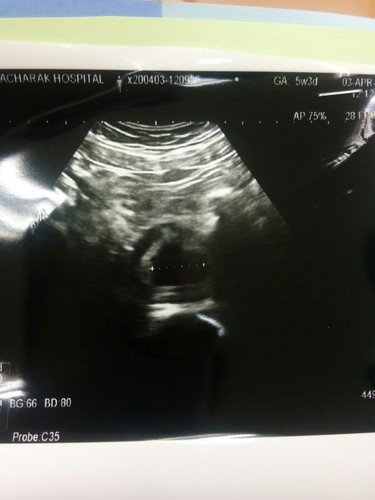

อัลตราซาวด์เจอแค่ถุงอายุครรภ์ 5 วีค

มีแม่ๆเจอน้องช้าบ้างมั้ยคะ ตอนไปซาวด์คุณแม่เจอน้องกี่วีคกันบ้างคะ แม่บ้านนี้กลัวท้องลมมากค่ะ (อายุครรภ์ที่คุณหมอคำนวณ 5 วีคแต่ในใบซาวด์ 7 วีค คุณแม่เครียดมากค่ะ) ตอบทีนะคะ ???✌